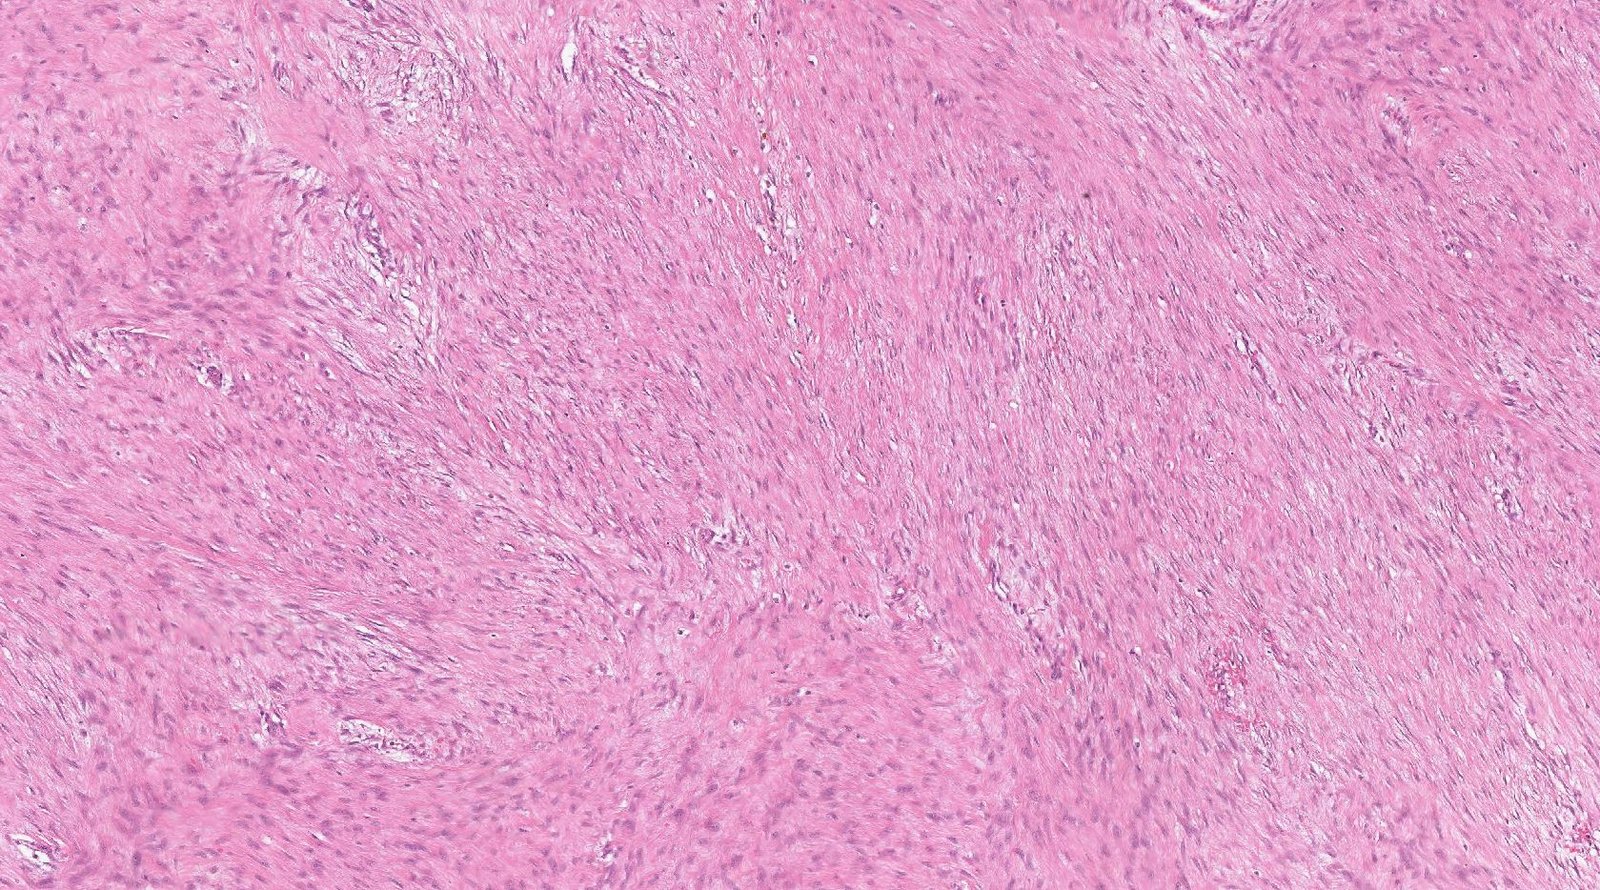

Case: AbdominalMass2

Final Diagnosis: